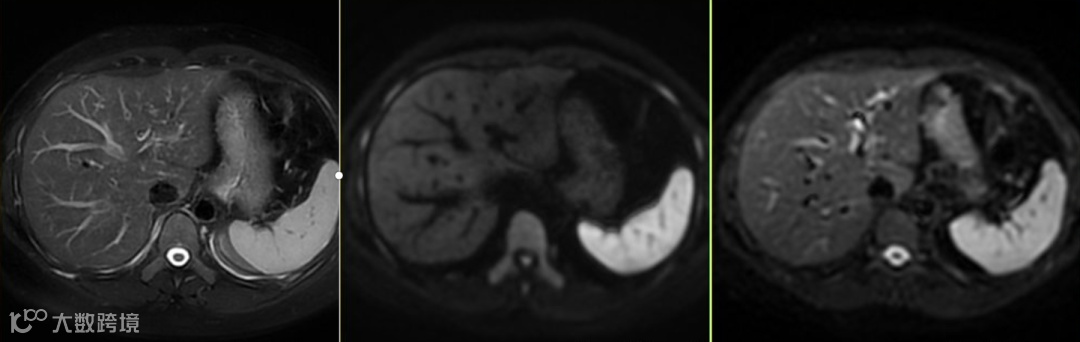

要区分脾脏的高信号是生理性的还是病理性的(如脾梗死、淋巴瘤、转移瘤),在选取正确的参照对比组织的同时,必须结合ADC图进行分析,上图△正常脾脏的DWI图像表现;分别DWI,ADC,eADC图像。